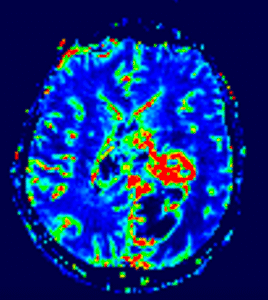

Pe lângă secvențele convenționale, tehnicile avansate aduc informații suplimentare:

- perfuzia evidențiază angiogeneza tumorală

- spectroscopia reflectă metabolismul celular

- DTI (tractografia) arată relația cu tracturile din substanța albă

Cu toate acestea, niciuna dintre aceste metode nu poate delimita complet infiltrarea microscopică. De aceea, planificarea chirurgicală și terapeutică trebuie să țină cont de această limitare.